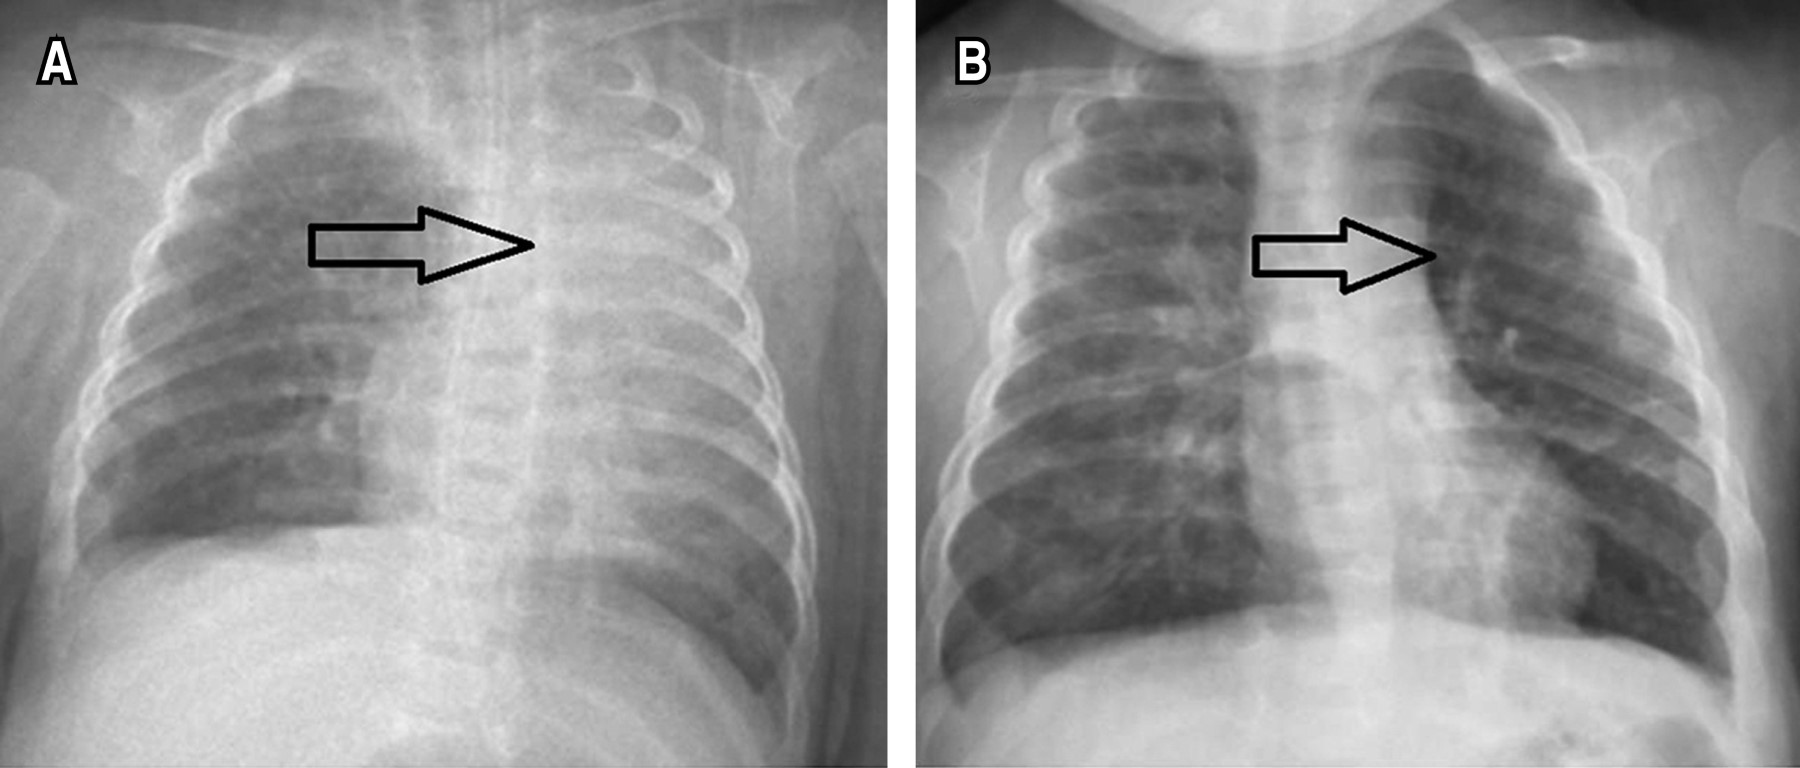

En los pacientes que se tomaron radiografías antes y después del tratamiento, se documentó mejoría. Los cambios más significativos al quinto día de tratamiento fueron la reexpansión parcial o total del pulmón colapsado, desaparición o reducción de los signos de opacidad pulmonar, y el posible desplazamiento de las fisuras interlobares y el mediastino hacia su posición normal (Figura 2). Sólo dos RN (6.9%) presentaron efectos adversos (broncoespasmo transitorio), pero no requirieron suspensión de la terapia.

La alfa-dornasa es una enzima que hidroliza el ADN extracelular presente en las secreciones, lo cual explica la mejoría, ya que reduce la viscosidad del moco y facilita la remoción de tapones mucosos, disminuyendo así la obstrucción bronquial.18,19 Por la naturaleza retrospectiva del estudio, no se dispuso de la evaluación radiográfica pre y postratamiento en todos los pacientes. Sin embargo, en el subgrupo que sí se dispuso de la información, la mejoría en los parámetros de oxigenación se asoció con mejoría radiológica evidente. Pero ante la falta de una evaluación radiológica sistemática en todos los pacientes, no se puede afirmar de manera concluyente que hubo resolución anatómica completa de las atelectasias en todos los casos. Futuros estudios deberán incluir la evaluación por imágenes seriadas, a fin de comprobar nuestros hallazgos.